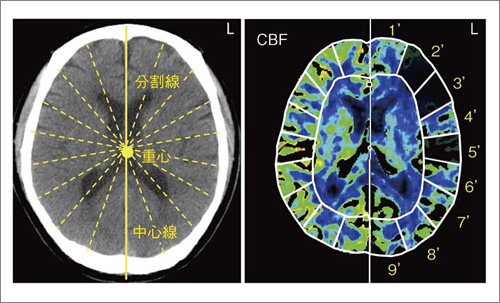

そこで図2に示すように,CT画像の中心線を決定することで,重心および分割線を自動設定し,健側と患側に左右対称にROIを設定する自動対側比評価法を開発した。しかも,左右のROIの対側比が,ある閾値以上(設定値は任意)の領域を強調表示することで,観察者やROI設定者の主観が入らず,かつ,設定が簡便なCTPの定量評価が期待される。

中心線を決定することで,重心および分割線を自動設定する。黒く表示されたROIが,ある閾値以上(設定値は任意)の領域である。